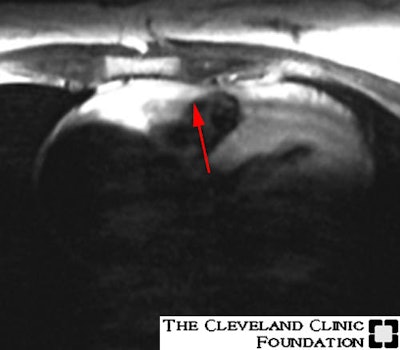

Arrhythmogenic Right Ventricular Dysplasia: Case 1

(Case courtesy of Dr. Scott Flamm, MD)Axial T1W images with a coronal saturation band through the left ventricle. The red arrows point to fatty infiltration within the myocardium of the high body (#1) and the low infundibulum (#2) of the right ventricle:

Image 2: